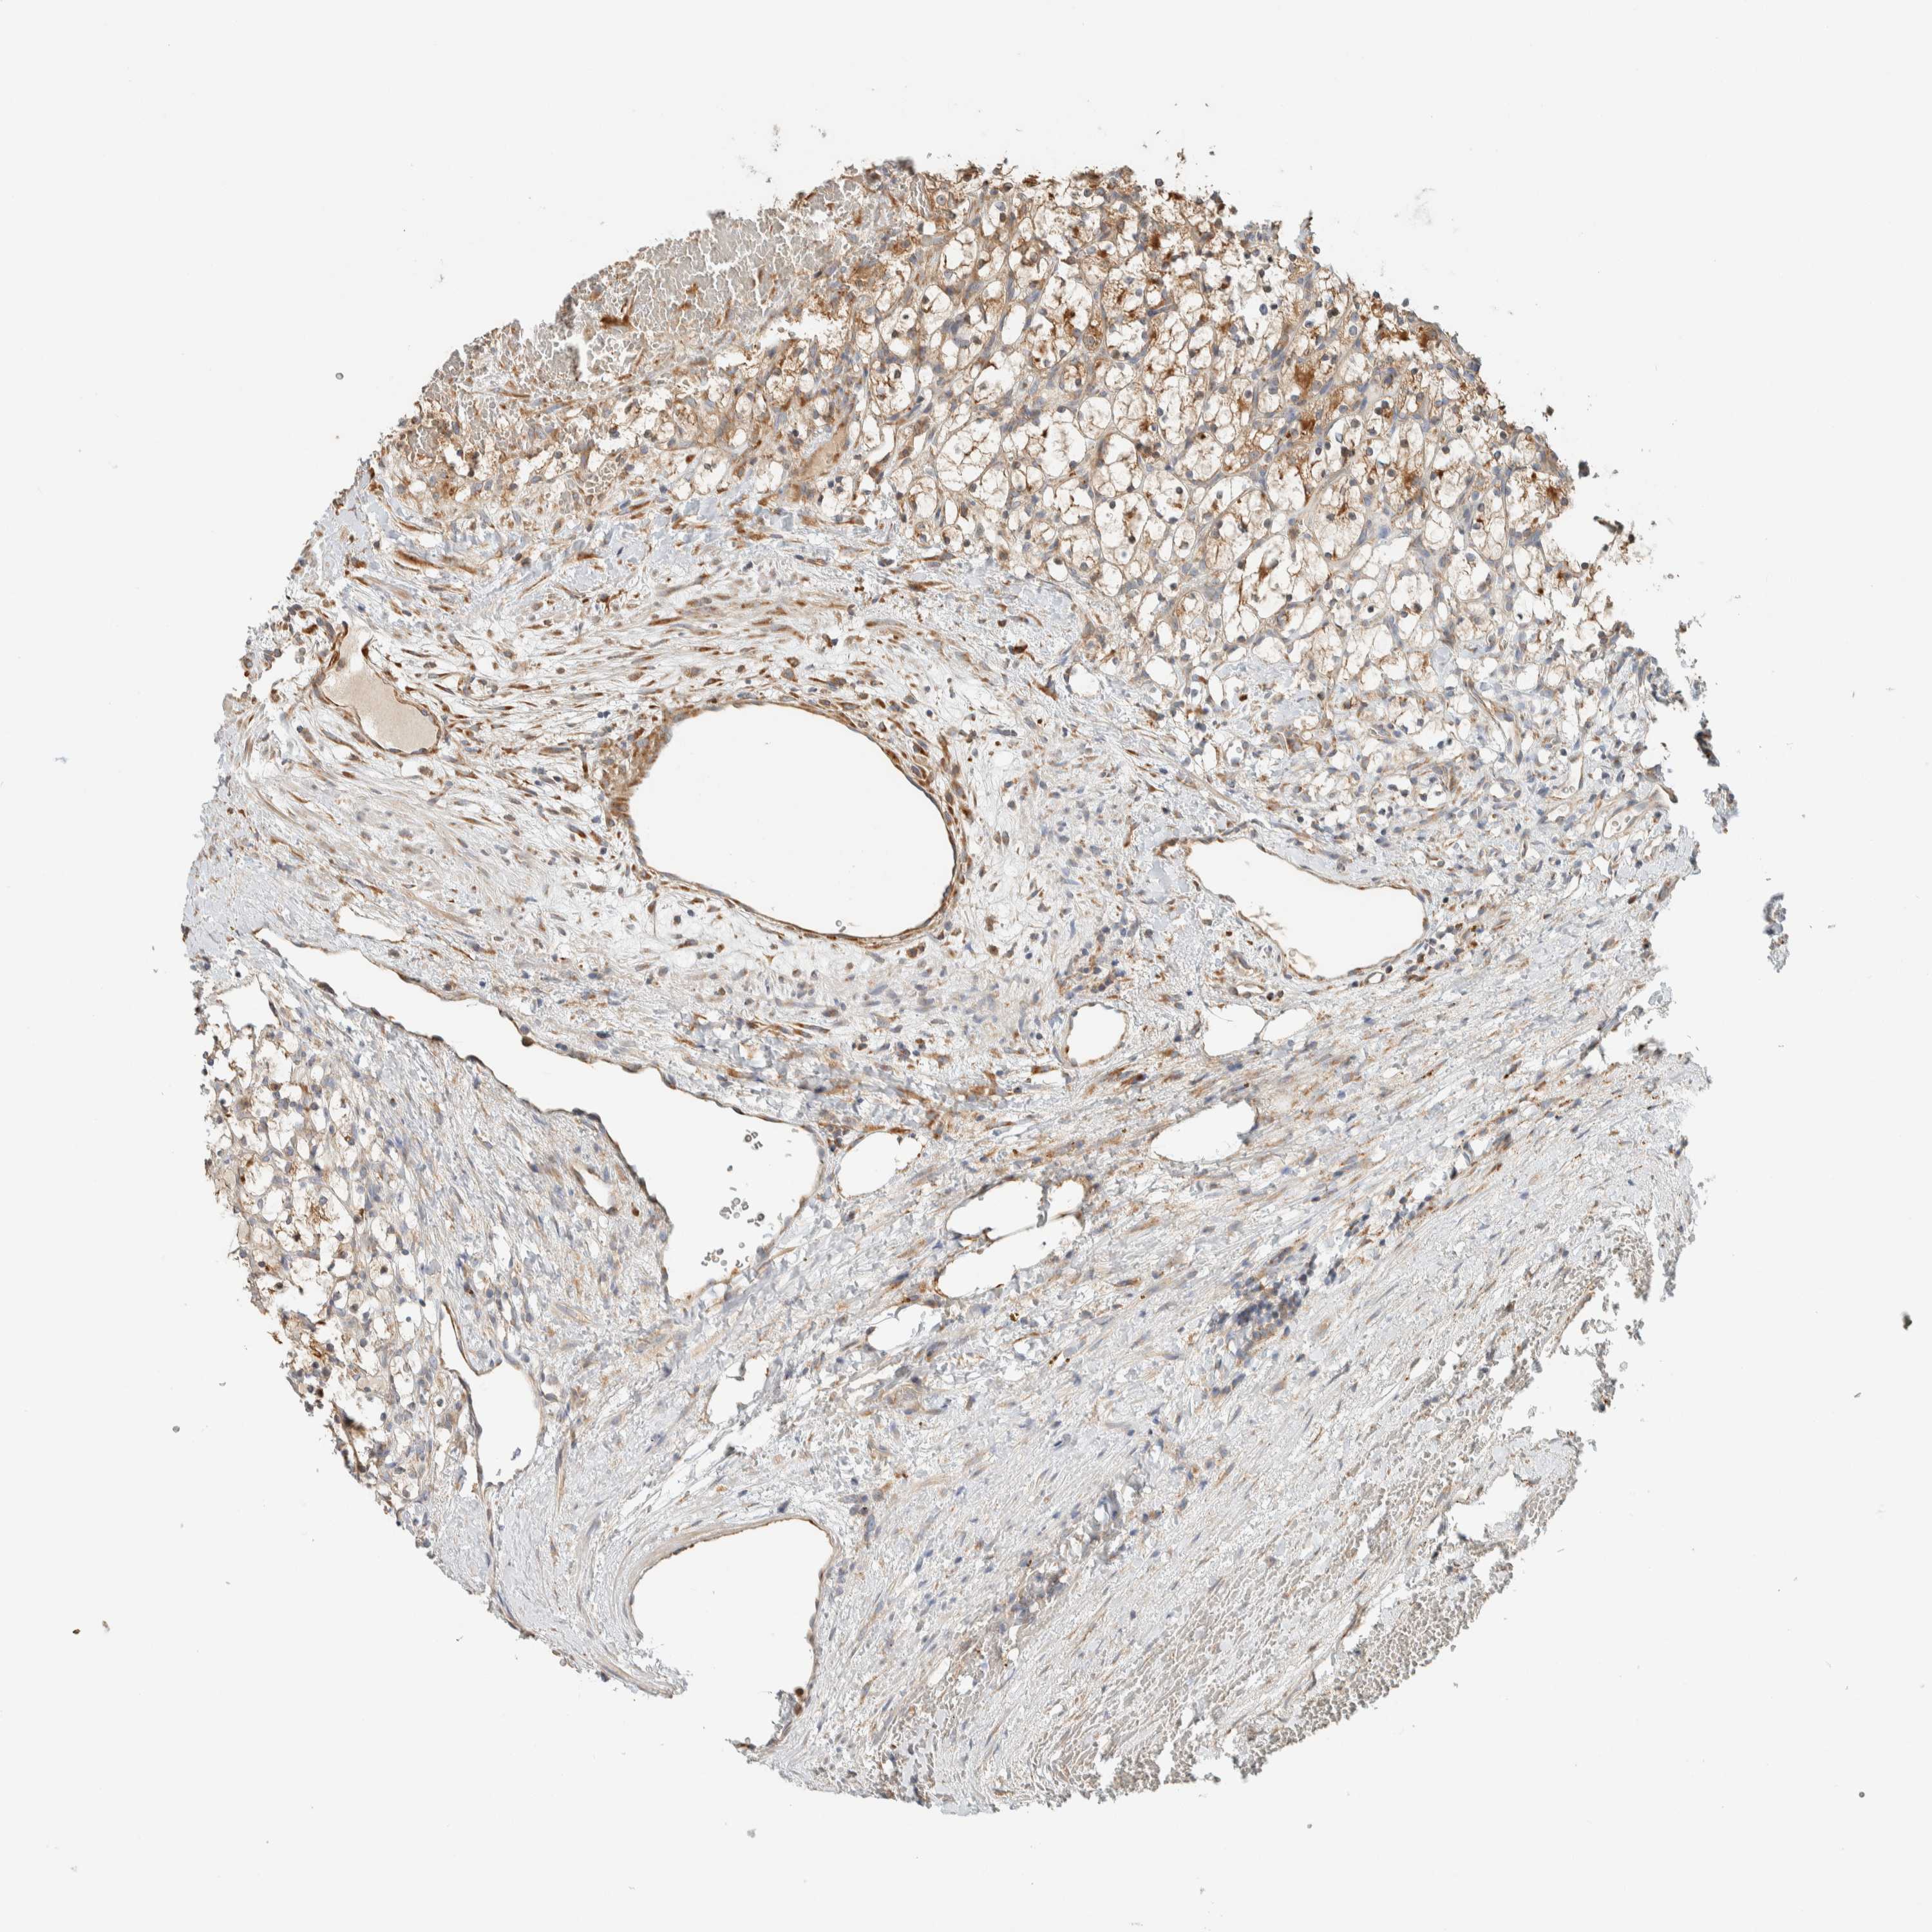

KIDNEY RENAL CLEAR CELL CARCINOMA (TCGA) - Interactive survival scatter ploti

The Survival Scatter plot shows the clinical status (i.e. dead or alive) for all individuals in the patient cohort, based on the same data that underlies the corresponding Kaplan-Meier plots. Patients that are alive at last time for follow-up are shown in blue and patients who have died during the study are shown in red.

The x-axis shows the expression levels (FPKM) of the investigated gene in the tumor tissue at the time of diagnosis. The y-axis shows the follow-up time after diagnosis (years). Both axes are complimented with kernel density curves demonstrating the data density over the axes. The top density plot shows the expression levels (FPKM) distribution among dead (red) and alive patients (blue). The right density plot shows the data density of the survived years of dead patients with high and low expression levels respectively, stratified using the cutoff indicated by the vertical dashed line through the Survival Scatter plot. This cutoff is automatically defined based on the FPKM cutoff that minimizes the p-score. The cutoff can be changed by dragging the vertical line or by entering a cutoff value in the square labeled "Current cut-off".

Under the Survival Scatter plot the p-score landscape (black curve; left axis) is shown together with dead median separation (red curve; right axis). Dead median separation is the difference in median mRNA expression between patients who have died with high and low expression, respectively. It is calculated as follows: median FPKM expression of dead patients with high expression - median FPKM expression of dead patients with low expression. This is intended to aid the user in visually exploring custom cutoffs and the associated p-scores and dead median separation.

Individual patient data is displayed and can be filtered by clicking on one or more of the category buttons on the top of the page. Categories describing expression level and patient information include: high, low, alive, dead, female, male and tumor stages. The scale of the x-axis can be toggled between linear and log-scale by clicking on the "x log" button. Mouse-over function shows TCGA ID, patient information and mRNA expression (FPKM) for each patient.

& Survival analysisi

Kaplan-Meier plots summarize results from analysis of correlation between mRNA expression level and patient survival. Patients were divided based on level of expression into one of the two groups "low" (under cut off) or "high" (over cut off). X-axis shows time for survival (years) and y-axis shows the probability of survival, where 1.0 corresponds to 100 percent.

RAB11FIP1 is potential prognostic, high expression is favorable in Kidney Renal Clear Cell Carcinoma (TCGA)

Best expression cut offi

Based on the FPKM value of each gene, patients were classified into two groups and association between prognosis (survival) and gene expression (FPKM) was examined. The best expression cut-off refers the FPKM value that yields maximal difference with regard to survival between the two groups at the lowest log-rank P-value. Best expression cut-off was selected based on survival analysis .

When clicking on this number, the vertical dashed line indicating cut-off, the interactive survival plot, and the Kaplan-Meier curve will be adjusted to show results based on the best expression cut-off.

: 9.21

P scorei

Log-rank P value for Kaplan-Meier plot showing results from analysis of correlation between mRNA expression level and patient survival.

N/A

TCGA RNA samplesi

RNA-seq data is reported as average FPKM (number Fragments Per Kilobase of exon per Million reads), generated by the The Cancer Genome Atlas (TCGA) .

Normal distribution across the dataset is visualized with box plots, shown as median and 25th and 75th percentiles. Points are displayed as outliers if they are above or below 1.5 times the interquartile range. FPKM values of the individual samples are presented next to the box plot.

Average pTPM 14.4

Number of samples 521